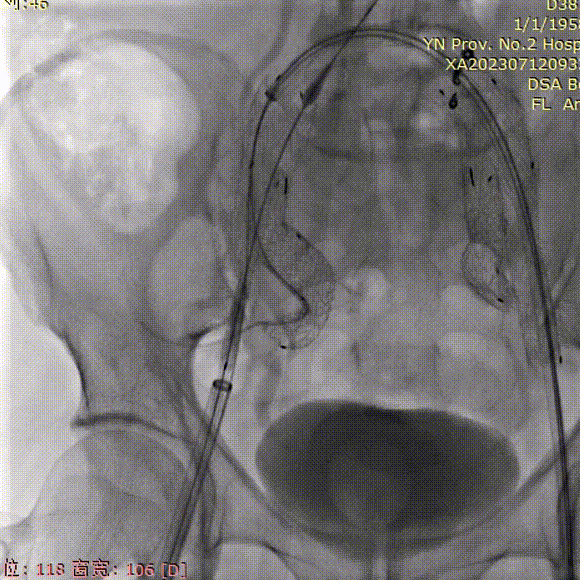

植入右侧IBE

右髂总动脉血栓较厚,造影观察无法明确髂内动脉开口位置,因此需要将IBE主体高放:

1. 顺着右侧硬导丝及牵张导丝,将IBE主体推送至右髂总位置;

2. 解缠绕后用“黄金圈”对准髂内开口方向并适当高放;

3. 超选右侧髂内动脉。

导管内手推造影,确认右髂内超选成功;

右髂内支架通过IBE短腿后,整体往下拉IBE,将IBE短腿拉至右髂内动脉开口上方;